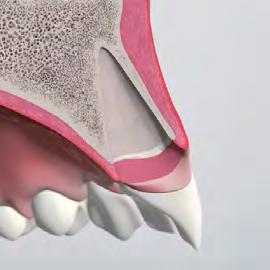

When grafting is indicated, the choice of technique and biomaterials depends on whether the buccal bone wall is preserved or compromised.

Preserved buccal wall ↷

Fill the Gap: stabilize the clot and support ridge contour stability.

Defective buccal wall <5 mm ↷

Fill + Protect: stabilize the clot and limit soft-tissue ingrowth to support esthetics.